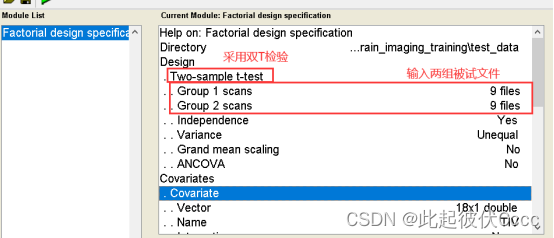

(1)点击上图中的圈1(Specify 2nd-level)按钮,进入以下界面:

(2)双击Directory,这个是需要你选择你的输出结果放置的文件夹

(3)点击Design,选择two-sample t-test,接下来给Group 1 scans和Group 2 scans导入被试的结构特征数据。

以TIV(之前在2.4步保存的文件)、年龄、性别作为协变量回归。(注意顺序)